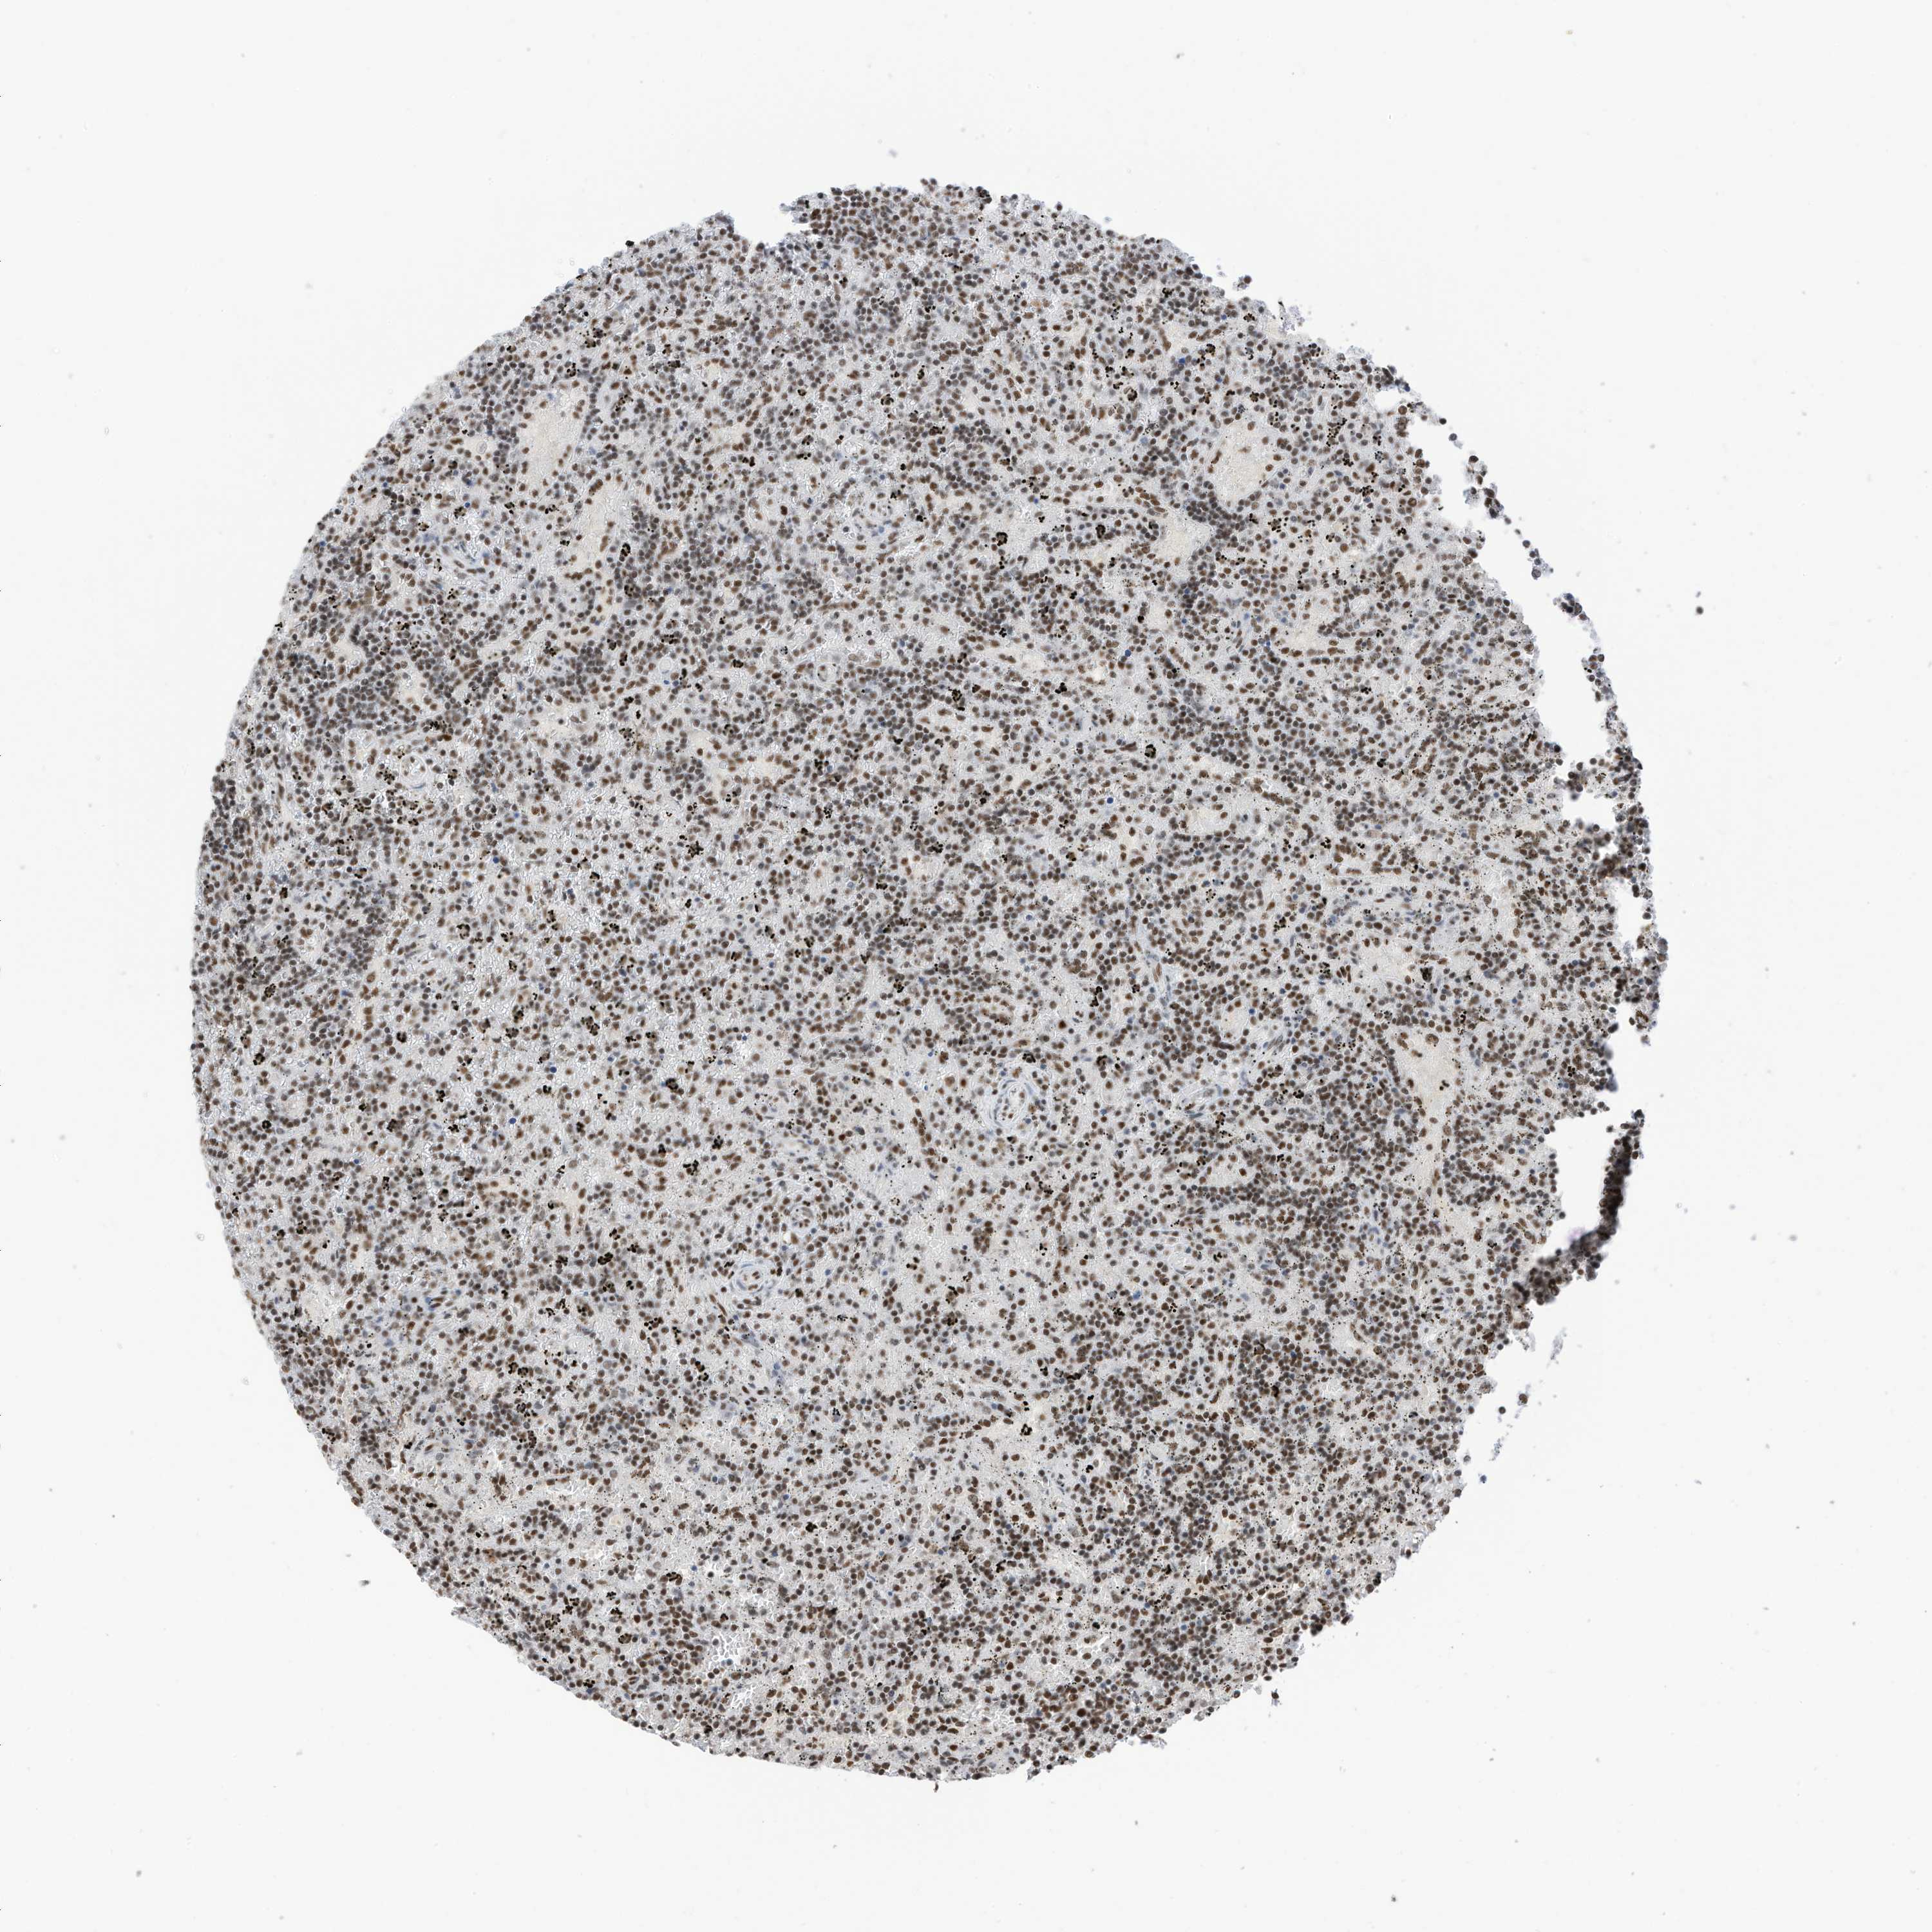

LYMPHOMA - Protein expressioni

A mouse-over function shows sample information and annotation data. Click on an image to view it in a full screen mode. Samples can be filtered based on level of antibody staining by selecting one or several of the following categories: high, medium, low and not detected. The assay and annotation is described here.

Antibody stainingi

Antibody staining in the annotated cell types in the current human tissue is reported as not detected, low, medium, or high, based on conventional immunohistochemistry profiling in selected tissues. This score is based on the combination of the staining intensity and fraction of stained cells.

Each image is clickable and will lead to virtual microscopy that enables deeper exploration of all samples and also displays staining intensity scores, fraction scores and subcellular localization as well as patient and tissue information for each sample.

Antibody HPA032054

Staining

High

Intensity

Strong

Quantity

>75%

Location

Nuclear

Hodgkin's disease, NOS

Malignant lymphoma, non-Hodgkin's type, High grade

Malignant lymphoma, non-Hodgkin's type, Low grade